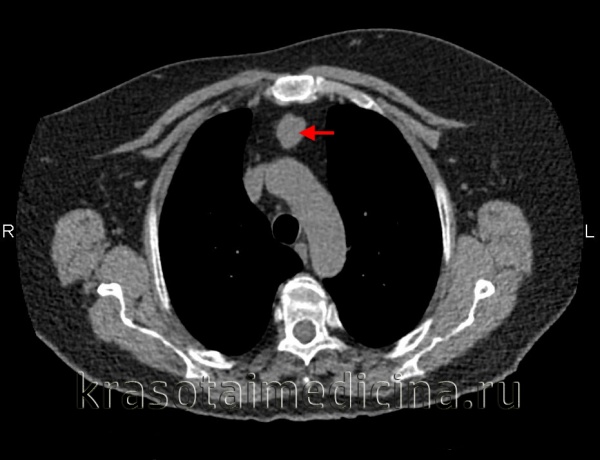

Расширение тени средостения на обзорном снимке влево в области аорто-пульмонального окна, в области талии сердца и при томографическом исследовании прекрасно виден конгламерат увеличенных лимфатических узлов, которые располагаются в переднем средостении. Объемные образования, которые состоят из множества лимфатических узлов, отличают такой процесс от обычных опухолей средостений.

С другой стороны, эти лимфатические узлы могут вырастать в патологическое образование, которое совершенно неотличимо ни от каких других опухолей средостений, с признаками инвазии, с вовлечением в грудной стенке, со сдавлением крупных сосудов, со стеснением и сужением трахеи главных бронхов.

Другой пример. Болезнь Кастельмана. Здесь специально оставлены денситометрические показатели. Средняя плотность образования, которое располагается между типичных образований, между восходящей и нисходящей аортой и оттесняет трахею сзади и справа, составляет почти 140 или 150 единиц (неразборчиво, 15:07).

Практически так же как контрастированная кровь. Очень немногие патологические образования средостения реагируют таким образом на введение контрастного вещества. В этом случае сочетание точной локализации и реакции на контрастный препарат позволяют предположить правильный диагноз.